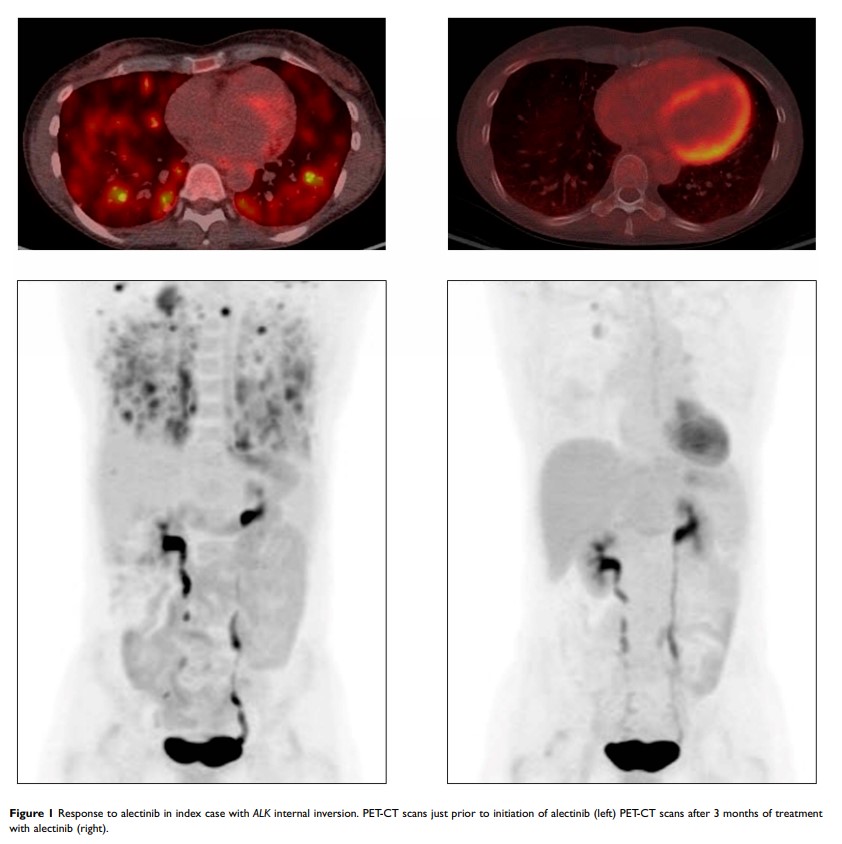

Patients with NSCLCs Harboring Internal Inversions or Deletion Rearrangements of the ALK Gene Have Durable Responses to ALK Kinase Inhibitors